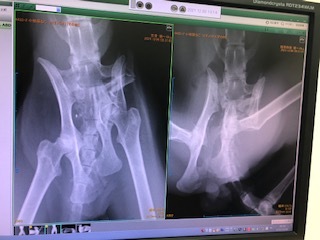

すぐさま動物病院へ行きレントゲンを撮ると、骨盤骨折、肺に影、膀胱が傷付き、便の通り道にも影響がでているかもしれない、

※左の骨盤折れています。